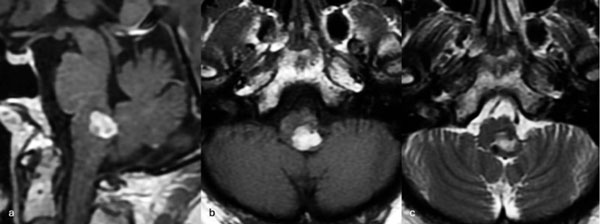

Figura 9. RM preoperatoria de encéfalo. Se evidencia una lesión única intraaxial bulbotrigonal izquierda, que contacta la mitad inferior del piso del cuarto ventrículo, hiperintensa en T1 y T2, con vacíos de flujo que impresionan provenir de una malformación del desarrollo venoso, lo que sugiere una malformación cavernomatosa. A) Imagen en corte sagital ponderada en T1 posterior a la administración de gadolinio. B y C) Imágenes en corte axial ponderadas en T1 y T2, respectivamente.

Caso 4: cavernoma bulbar

Una mujer de 53 años, con antecedentes de dos sangrados previos, consultó por un cuadro de perfil agudo caracterizado por tetraparesia asociada a compromiso de pares craneales bajos, que requirió instalación de una traqueostomía. La RM de encéfalo evidenció una malformación cavernomatosa en relación al bulbo izquierdo (Figura 9). Un mes después del último sangrado, la paciente fue sometida a una exéresis de la lesión mediante un abordaje suboccipital de línea media, vía intertonsilar (Figura 10), logrando una exéresis completa (Figura 11). Luego de la cirugía la paciente evolucionó con mejoría parcial de sus síntomas de ingreso, sin agregar nuevos déficits neurológicos.